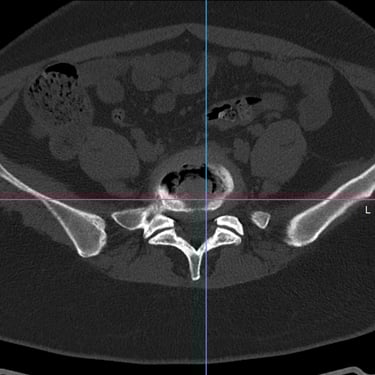

Manejo quirúrgico de la hernia lumbar con inestabilidad: enfoque moderno con FTP y TLIF

La hernia lumbar con inestabilidad vertebral es una patología frecuente que causa dolor lumbar persistente, ciática y limitación funcional, afectando la calidad de vida del paciente. Cuando el tratamiento conservador no logra resultados adecuados, la cirugía se convierte en la mejor opción terapéutica. La fijación transpedicular con tornillos (FTP) junto con la técnica TLIF (Transforaminal Lumbar Interbody Fusion) permite estabilizar la columna, descomprimir las estructuras nerviosas y lograr una adecuada fusión ósea. Este abordaje, especialmente mediante técnicas mínimamente invasivas (MISS), ofrece múltiples beneficios, como menor daño muscular, menor dolor postoperatorio y recuperación más rápida, facilitando el retorno temprano a las actividades cotidianas con mejores resultados clínicos.